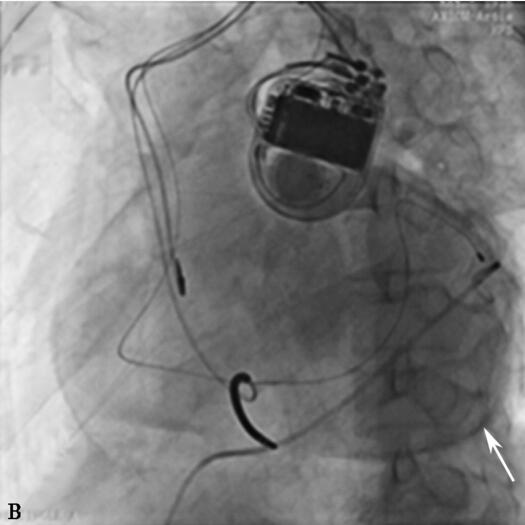

入院心电图:窦性心律,完全性左束支传导阻滞,QRS波时限200ms。心脏超声:左室射血分数:0.32,左心室内径:77mm,室壁运动幅度普遍减低。诊断:①扩张性心肌病:心功能Ⅲ级;②完全性左束支传导阻滞。根据器械植入指南,该患者为行CRT或CRT-D植入术的Ⅰ类适应证。在充分药物治疗基础上,心功能恢复至Ⅱ级水平,行CRT-D植入术(4193左室电极至心侧静脉远端),术中测试起搏电极参数良好,手术过程顺利,术后心电图:心房感知双心室起搏心电图。术后第二天患者下地活动自觉无不适,但患者心率偏快90次/分左右,心电图:间断左室不起搏,程控起搏电极参数左室阈值升高为3.0V(0.5ms),右室除颤电极及右房电极参数良好,给予提升左室输出电压后可见双心室完全起搏。同时给予控制心率、强心等相关药物治疗。术后第3日,患者出现心悸、胸闷、气短,伴膈肌跳动感,大汗。查体:端坐呼吸,口唇发绀,周身湿冷,血压85/60mmHg,双肺呼吸音粗,可闻及湿啰音,心率110次/分,律齐,心音遥远,可见膈肌跳动。心电图证实左室不起博,起搏器参数测试发现:最大电压7.5V(1.5ms)无法夺获左室,右室除颤电极及心房电极参数良好。患者心率快、血压低,心源性休克状态,考虑心包压塞可能性大,紧急推送导管室心脏透视,见中等量至大量心包积液(图3-5-2A),紧急行剑突下心包穿刺,应用猪尾导管心包腔引流,抽出200ml不凝血时患者症状较前缓解,共抽出不凝血约600ml,此时测血压:119/70mmHg,心率:80次/分,透视下见心包积液微量,连接心包负压吸引器后安返病房(图3-5-2B),此时查心脏超声:左室后壁后方心包腔内见6mm液性暗区。心包引流管通畅,患者无胸闷、心悸及胸痛不适,严密监测患者生命体征,6小时后复查心脏超声未见心包积液;同时继续抗心力衰竭、预防感染药物治疗。36小时后患者无不适主诉,生命体征平稳(停用升压药物),仍为房颤心律,连续两次复查心脏超声未见心包积液,24小时心包引流量5ml,给予拔出心包引流管。继续抗心力衰竭药物治疗,1周后患者一般状态较好,夜间气短、憋醒症状明显好转,病区内活动无胸闷、气短症状发作。患者因担心再次手术风险,拒绝进一步行调整左室电极导线手术。予以保留起搏器除颤功能,关闭了起搏功能后,病情好转出院。

B:经猪尾导管引流后心包腔内仅见微量造影剂残留